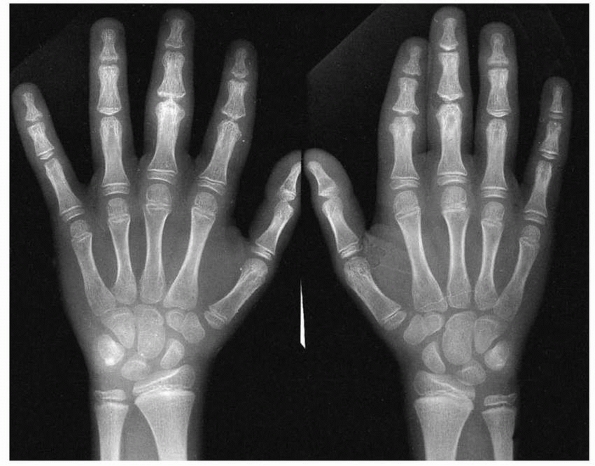

| Figure 5-9 Stress injury of the distal radius and ulna in both wrists of a competitive gymnast. There was no history of specific injury. The wrists were tender to touch. Note distal radial and ulnar physeal widening and irregularity. |